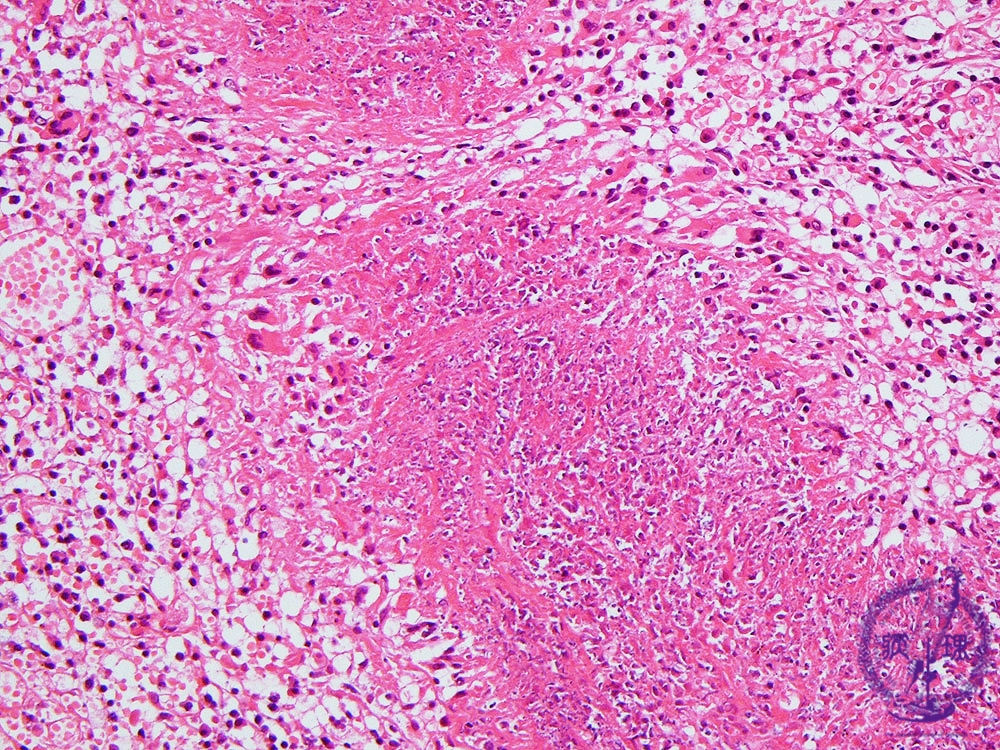

Microscopic view (intermediate power view): The typical histopathological finding is necrotizing granulomatosis demonstrated by necrotizing vasculitis and central necrosis with associated histiocytes, lymphocytes and multinucleated cells.